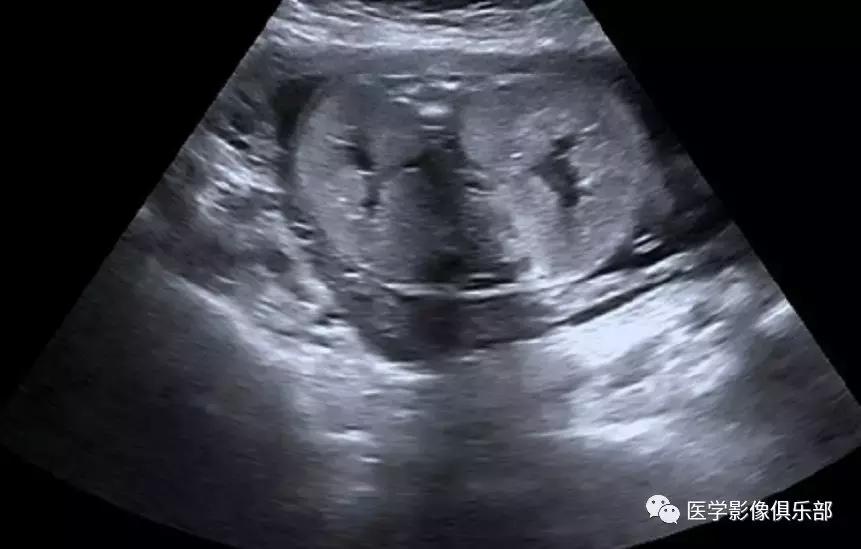

[病例举例]:25岁女性,双肾多发囊肿。

双侧肾脏皮质内数枚类圆形囊肿。